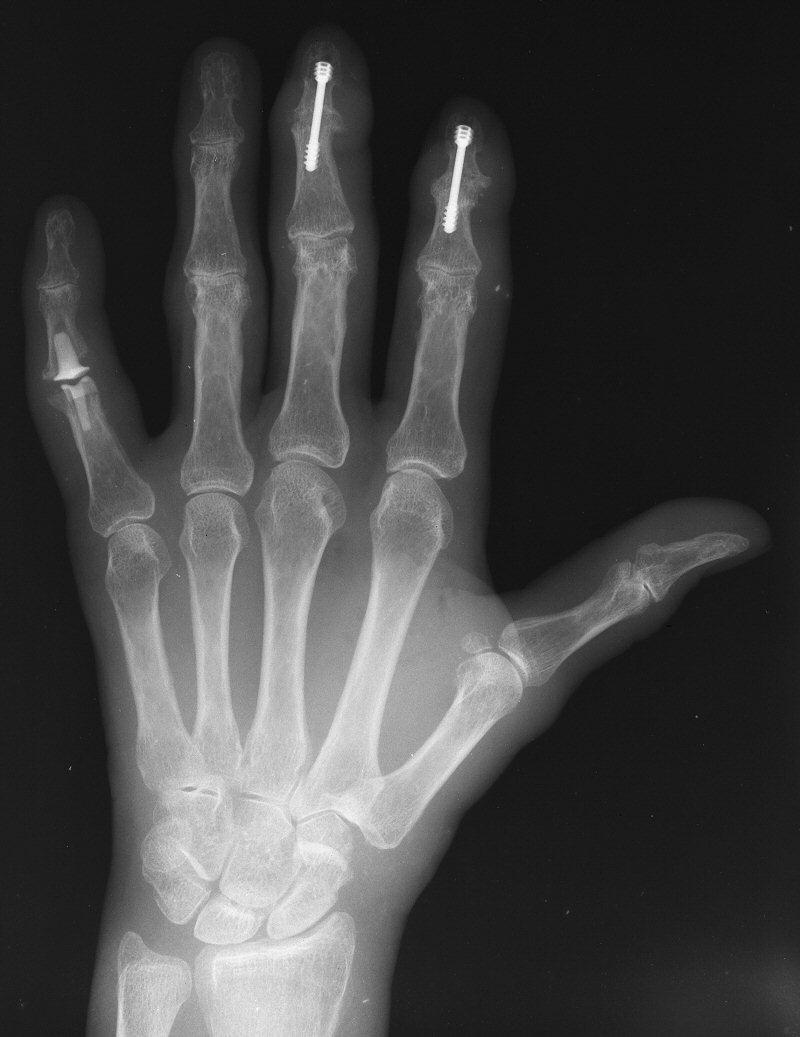

Arthritis Distal Interphalangeal Joint Arthroplasty with reversed Dip Joint Pinky Finger The lumps grow on the joint closest to the tip of your finger, called the distal interphalangeal, or dip joint. The middle joint, called the proximal interphalangeal (pip) joint; Diagnosis can be made clinically. The joint where the finger connects to the hand, called the metacarpophalangeal (mcp) joint; The dip joint in the finger is located at the tip of. Dip Joint Pinky Finger.

DIPJ Ring finger Fracture (Xray 34) YouTube Dip Joint Pinky Finger The middle joint, called the proximal interphalangeal (pip) joint; Phalanx dislocations are common traumatic injury of the hand involving the proximal interphalangeal joint (pip) or distal interphalangeal joint (dip). Diagnosis can be made clinically. Arthritis of the dip and pip joints are very common forms of osteoarthritis seen in the hand and can be associated with pain and deformity. Diagnosis. Dip Joint Pinky Finger.